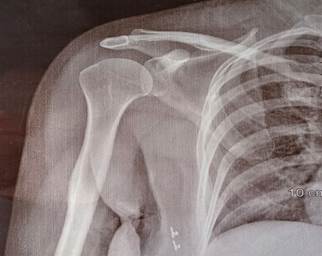

motion. In the radiographic image, the calcific deposit from the supraspinatus

tendon insertion was gone (Figure 2).

Figure

2. Anteroposterior external rotation radiograph of the

right shoulder, demonstrates marked improvement in the previously noted soft

tissue calcifications identified at the insertion site of the supraspinatus

tendon.

of movement, and size of calcification (12). In the current study, all three

variables were measured as treatment outcomes. All three parameters showed

dramatic changes after iontophoresis with 5% acetic acid. In particular, the

patient's pain score reached zero by the end of ten sessions, the shoulder

range of motion became fully restored, and the calcification resolved

completely.